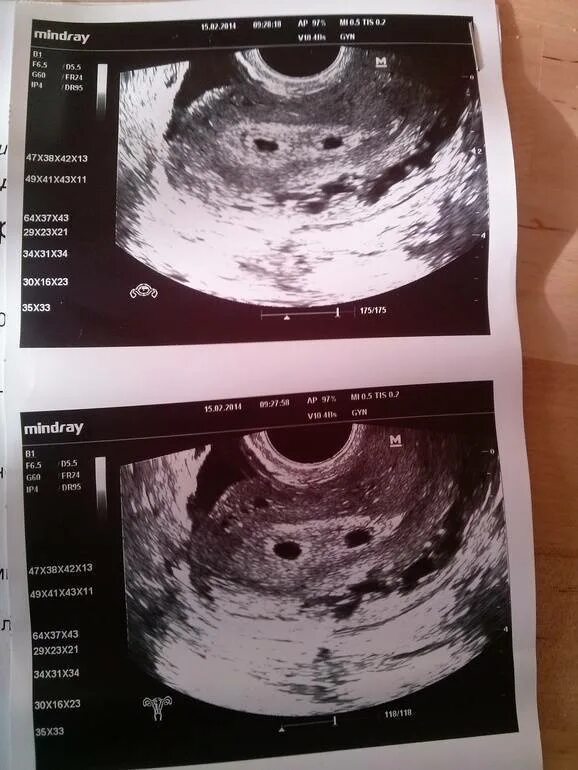

На каком сроке можно увидеть двойню